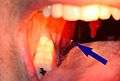

| A tonsillolith lodged in the tonsillar crypt | |

A tonsillolith protrudes from the tonsil- Large tonsillolith half exposed on tonsil